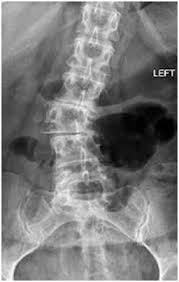

الأشعة السينية: لقياس زاوية كوب (Cobb Angle) التي تحدد درجة الانحناء بدقة.

التصوير بالرنين المغناطيسي أو الأشعة المقطعية: يستخدم في بعض الحالات لتقييم الأعصاب أو العظام بشكل أدق، خصوصًا عند الاشتباه في وجود سبب عصبي أو خلقي.